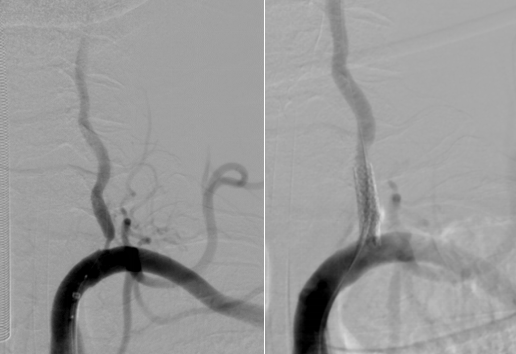

由于患者错过了4.5小时脑卒中静脉溶栓救治时间,无法溶栓治疗。郝永岗副主任带领神经血管介入团队评估病情后决定在全麻下为患者实施动脉取栓术,挽救处在缺血状态尚未坏死的脑组织。麻醉科李健主任第一时间到达导管室,保障手术顺利进行,术中可见患者基底动脉末端闭塞(基底动脉尖综合征)。医生运用SWIM技术取出黑红色血栓,复查造影显示:基底动脉远端血流通畅,双侧大脑后动脉、小脑上动脉显影。术中发现患者左侧椎动脉起始部重度狭窄,于病变处植入支架一枚,血管狭窄解除,术后送重症医学科继续治疗。